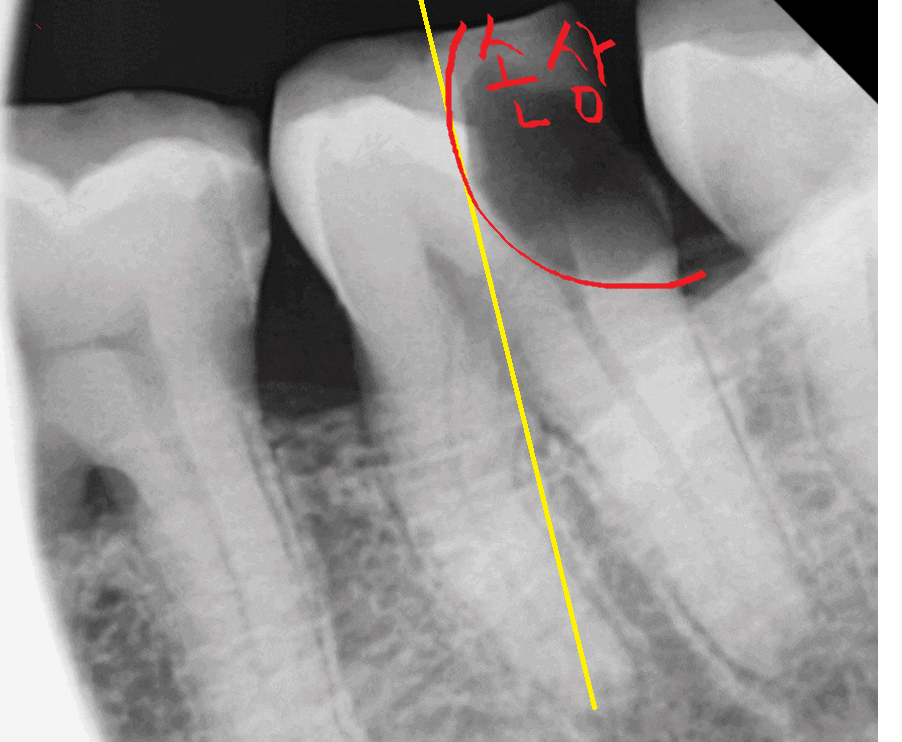

x-ray를 한장 더 찍어 보았습니다.

230918

절반을 비교해보았을 때

왼쪽과 오른쪽의 차이

느껴지시나요?

충치가 없는 부위는 하얗게 표시되지만

이가 썩게되면

충치 벌레가 내 치아 속을 다 파먹습니다.

내부가 텅~~비기 때문에

까맣게 보여지게 되는데요.

손상된 치아 부분

이제 눈에 확! 들어오시죠~?

충치가 절반 이상 먹었네요.

뿌리쪽까지 깊게 썩었는데요.